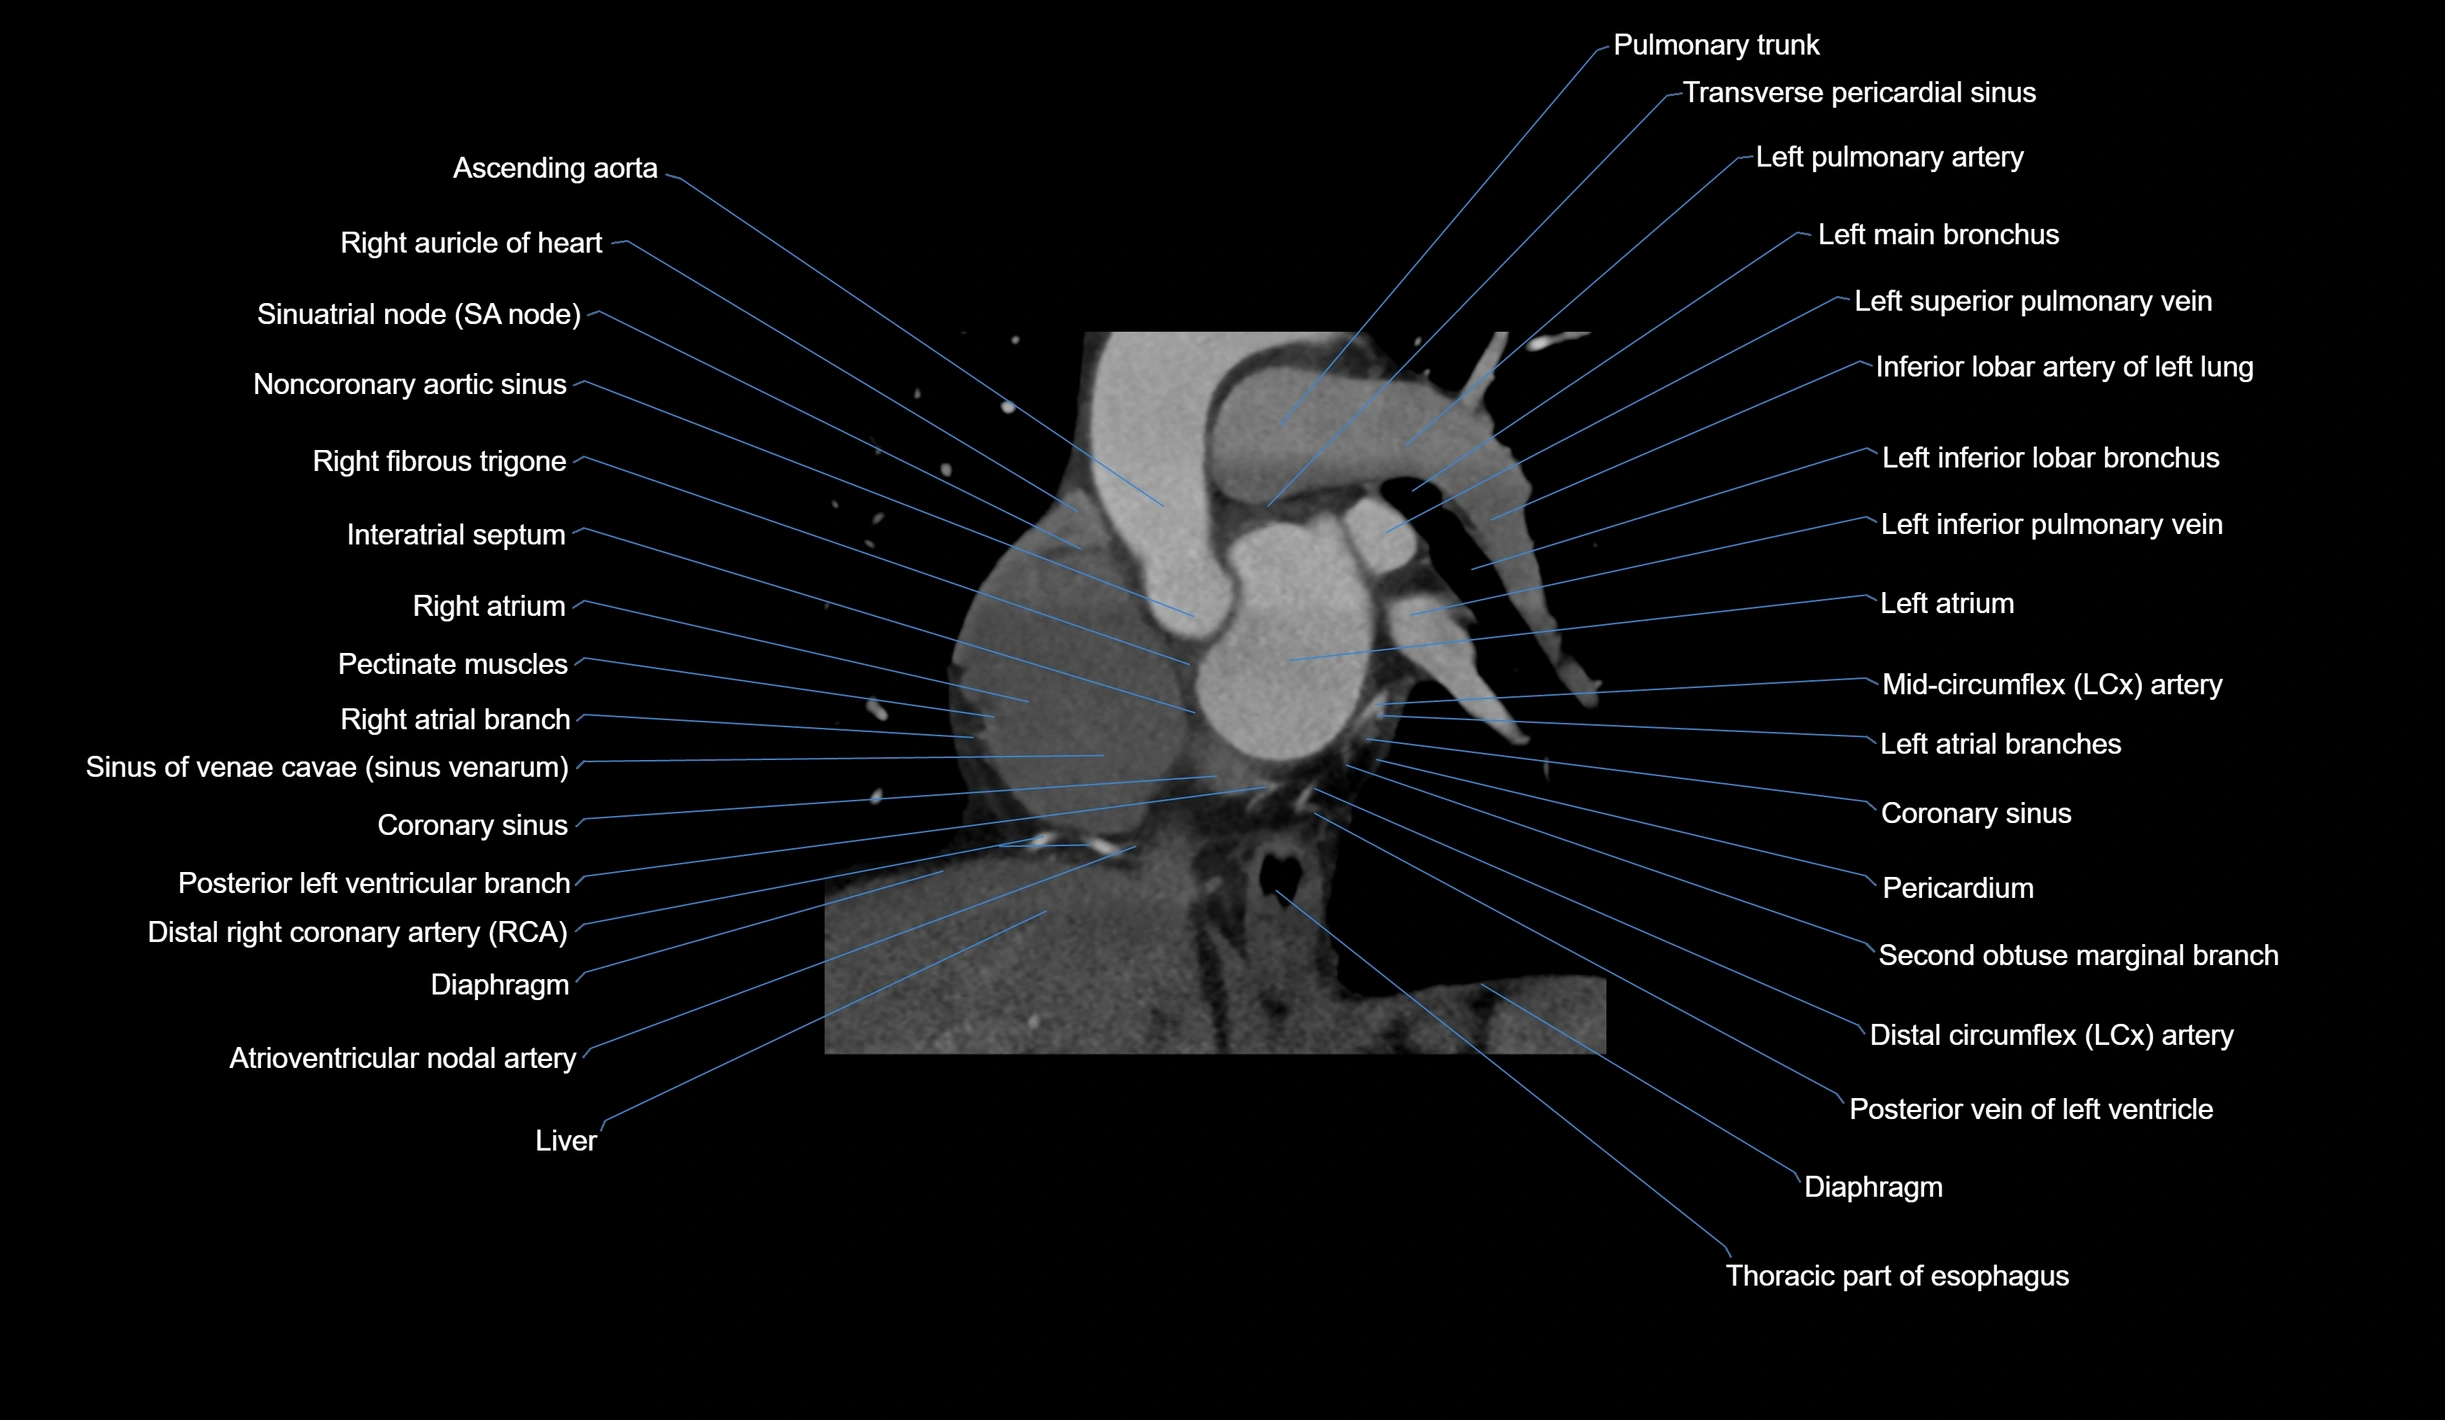

CT Appearance

Non-contrast CT (Calcium Scoring):

-

AM artery visualized for coronary calcium scoring

Calcified plaques appear as hyperdense foci; scored with Agatston method

CT Coronary Angiography (CCTA):

Best non-invasive modality for acute marginal artery visualization

Shows origin, course along the acute margin, and right ventricular branches

Detects stenosis, occlusion, calcified and non-calcified plaques, aneurysm, or anomalous course

Multiplanar reformats and 3D reconstructions help in pre-PCI and surgical planning

Critical for assessing right ventricular infarction risk in RCA disease

MRI image

CT images